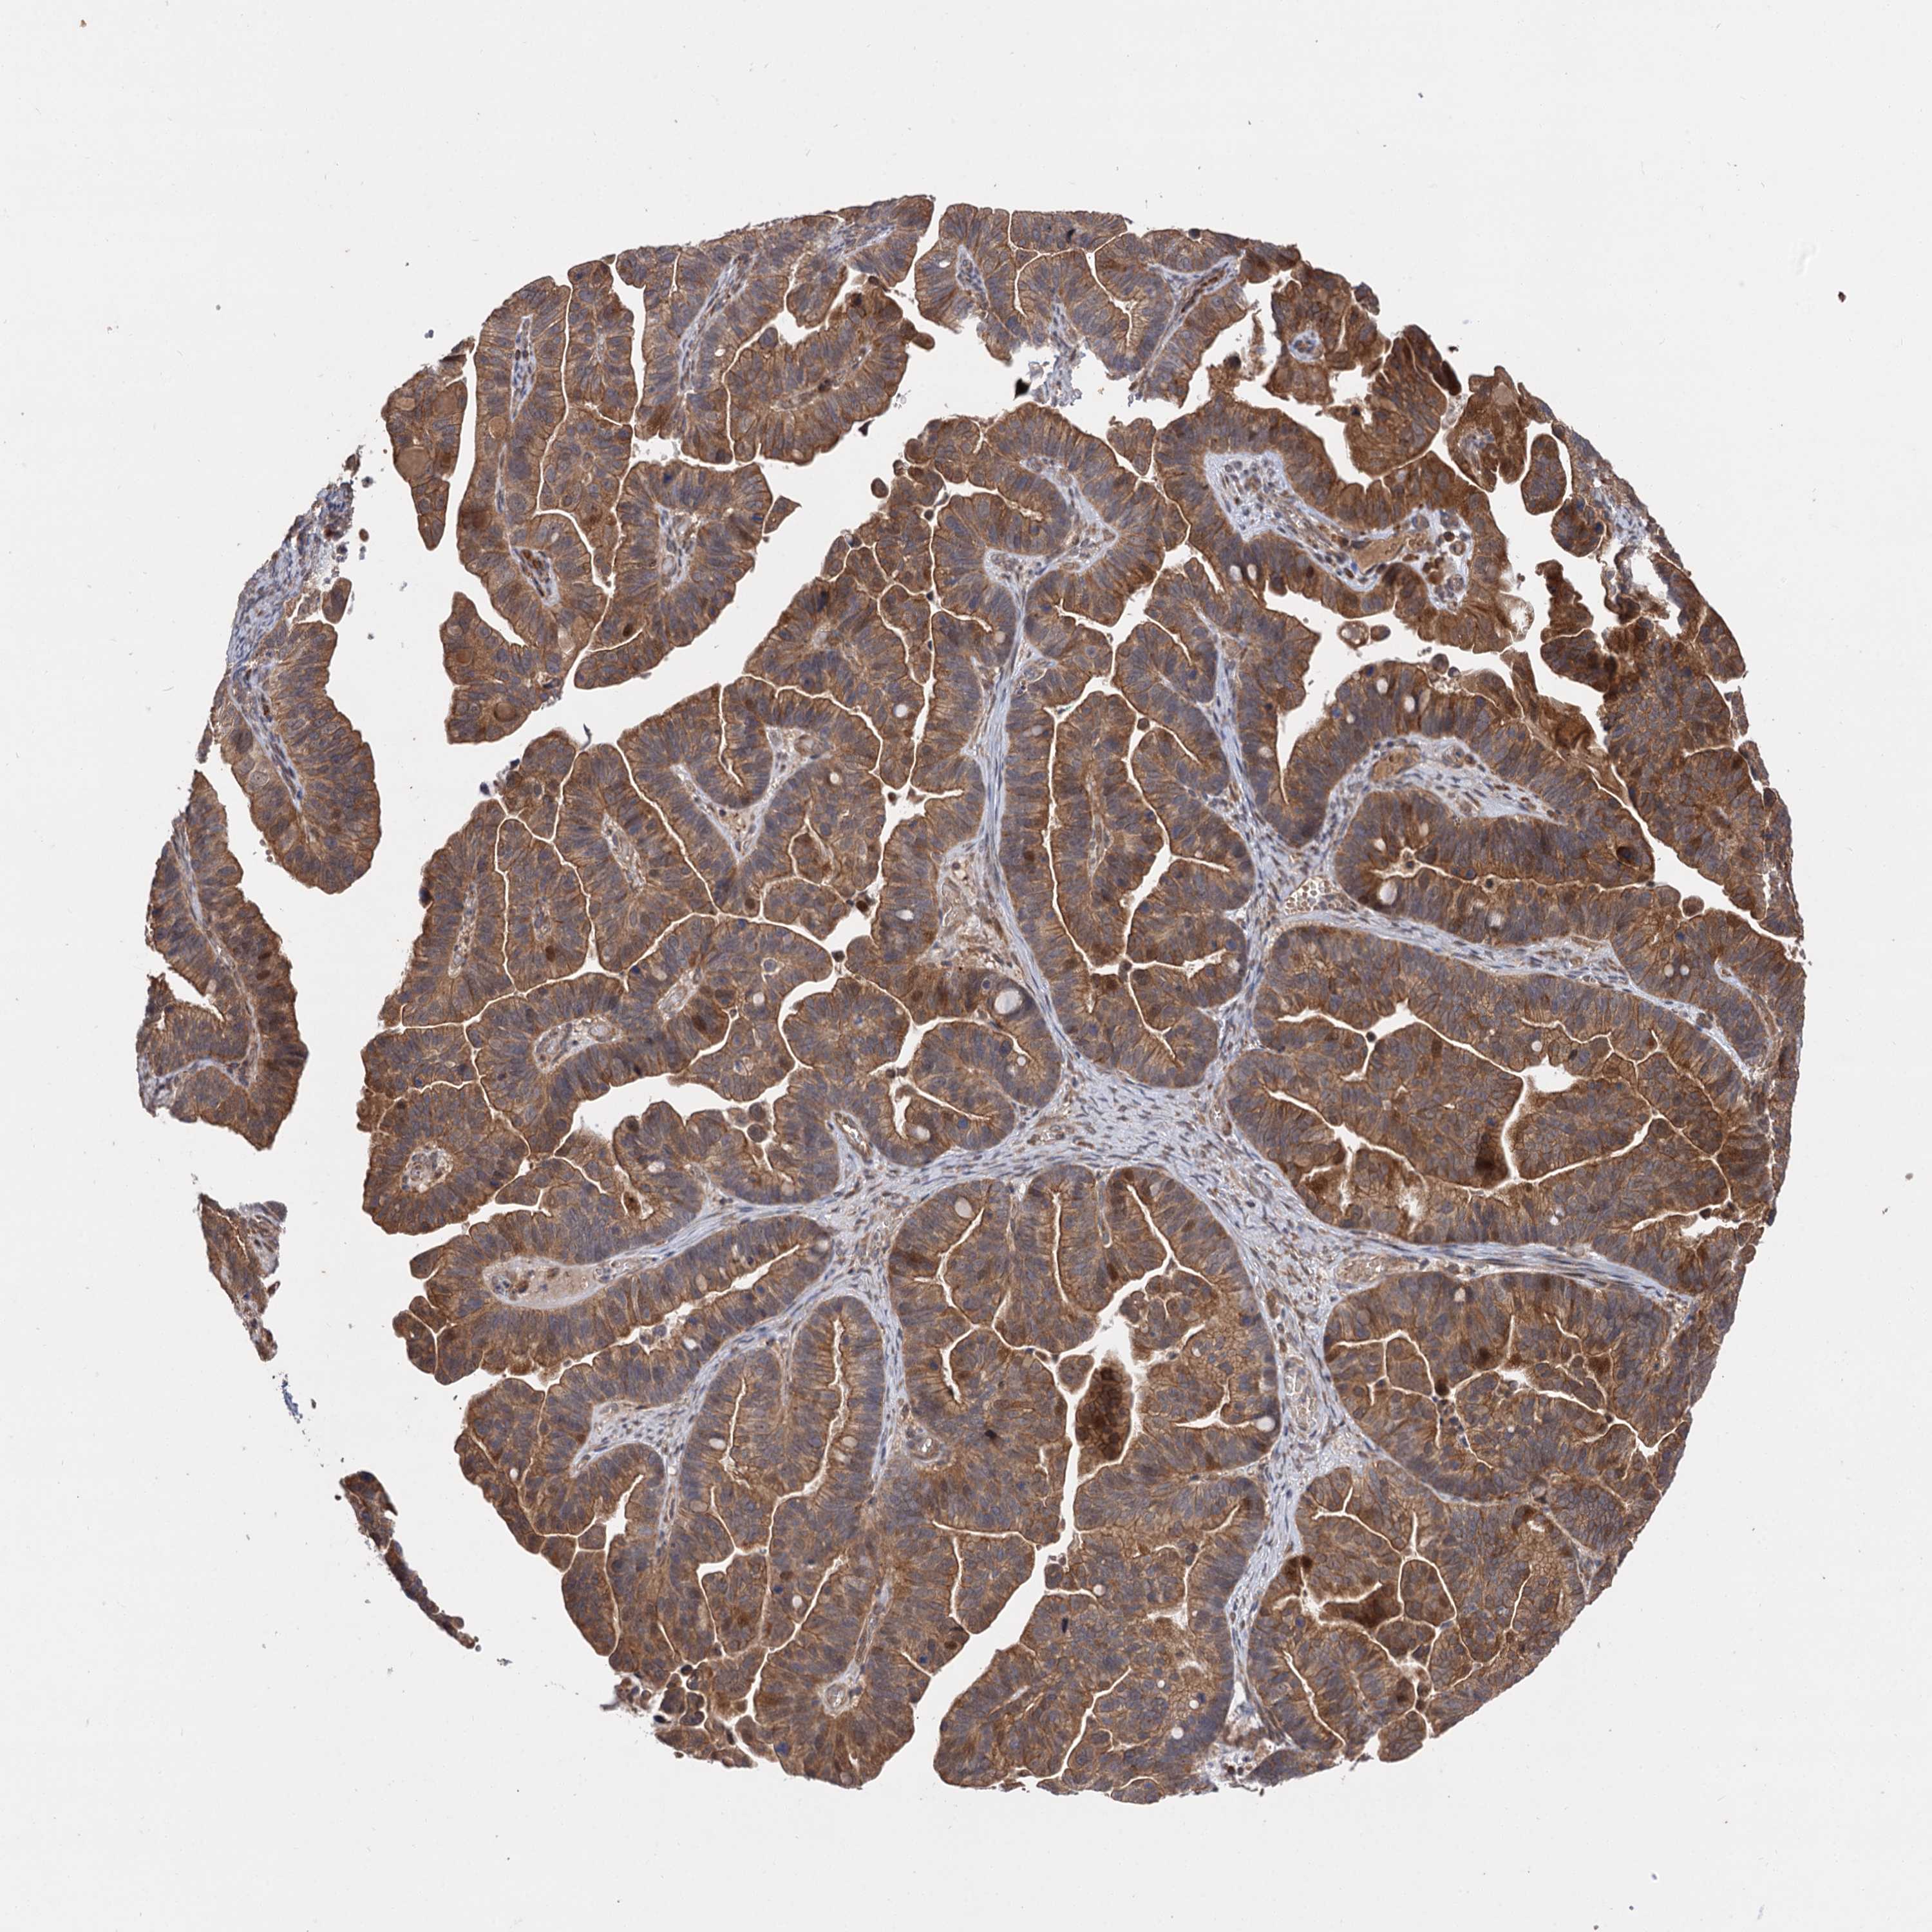

OVARIAN CANCER - Protein expressioni

A mouse-over function shows sample information and annotation data. Click on an image to view it in a full screen mode. Samples can be filtered based on level of antibody staining by selecting one or several of the following categories: high, medium, low and not detected. The assay and annotation is described here.

Note that samples used for immunohistochemistry by the Human Protein Atlas do not correspond to samples in the TCGA dataset.

Antibody stainingi

Antibody staining in the annotated cell types in the current human tissue is reported as not detected, low, medium, or high, based on conventional immunohistochemistry profiling in selected tissues. This score is based on the combination of the staining intensity and fraction of stained cells.

Each image is clickable and will lead to virtual microscopy that enables deeper exploration of all samples and also displays staining intensity scores, fraction scores and subcellular localization as well as patient and tissue information for each sample.

Antibody HPA038850

Antibody HPA038851

Cystadenocarcinoma, mucinous, NOS